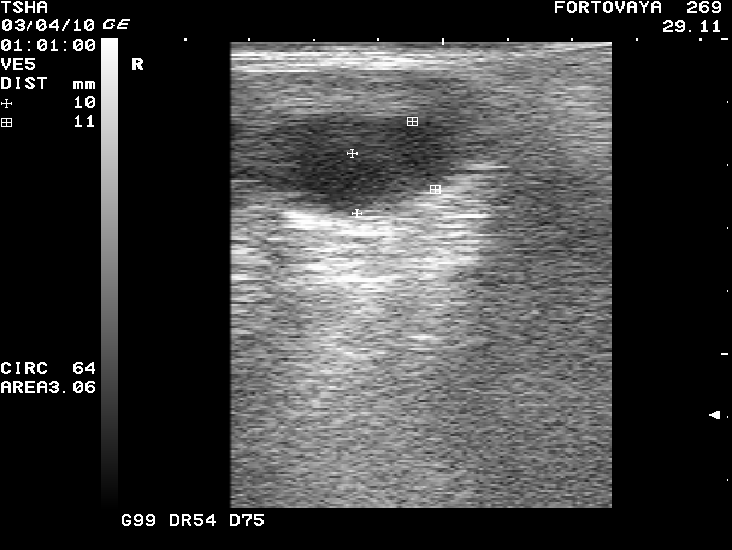

Рис. 6. Вариабельность параметров фолликуло - и кистогенеза у коровы Фартовая 269 с хронической формой кистозной болезни яичников. Сканирование яичников проводили через каждые 14 дней

При положительной реакции на лечение на 7-й день после введения овулина у 9-ти или 81,8% коров регистрировали формирование желтого тела солидного или кистозного типа в одном случае (9,1%) – образование двух желтых тел (рис.3), в другом – лютеинизацию стенки кисты с последующей ее регрессией и восстановлением овуляции.